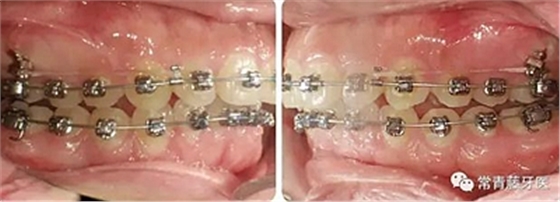

上下牙列輕度擁擠,牙弓偏尖圓形;前牙深覆合深覆蓋;雙側(cè)磨牙尖牙偏遠(yuǎn)中關(guān)系。

治療23個(gè)月結(jié)束??梢?jiàn)兩側(cè)尖磨牙達(dá)到中性關(guān)系,上下牙列排齊整平,前牙覆合覆蓋正常,中線(xiàn)齊。

結(jié)束3個(gè)月后復(fù)查,無(wú)明顯復(fù)發(fā)。